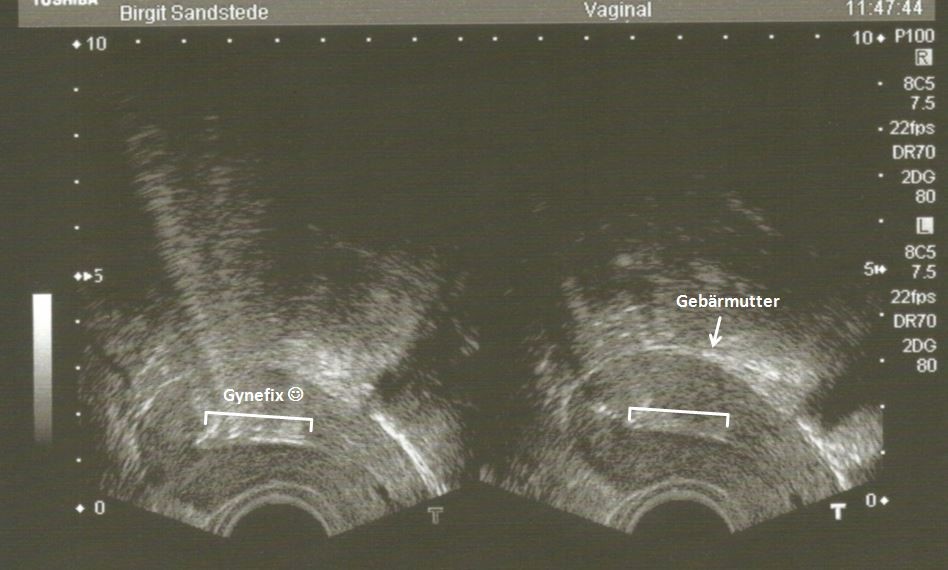

Mein erstes Ultraschallbild… es ist eine Gynefix ;-)

Ich hatte mit Frau Sandstede zuvor über meine Angst vor den Schmerzen gesprochen. In Absprache habe ich dann zwei Ibuprofen 400 präventiv gegen die Schmerzen genommen und eben zusätzlich noch die empfohlene Dosis Buscopan zur Entspannung des Bauchraums. Nachdem sie meine Gebärmutter vermessen (das habe ich gar nicht mitbekommen, so schnell ging das) und den Muttermund mit einem Gel desinfiziert und leicht betäubt hatte, wurde mir die Gynefix mini eingesetzt. Das hat zweimal kurz geziept. Einmal beim Strecken der Gebärmutter und dann natürlich beim Einstich und Drehen der Nadel. Das war zwar relativ fies und ich habe mich auch kurz erschrocken, aber danach war es auch direkt vorbei. Ich konnte sogar noch eine kleine Shopping-Tour in Frankfurt machen - allerdings war ich durch die Schmerzmittel schon etwas neben der Spur. Insgesamt ging es mir ganz gut nach dem Eingriff und ich war extrem froh und euphorisch, dass ich diesen Schritt endlich gewagt hatte! Und da ist sie nun auf meinem ersten Ultraschallbild, meine Begleitung für die nächsten 5 Jahre…